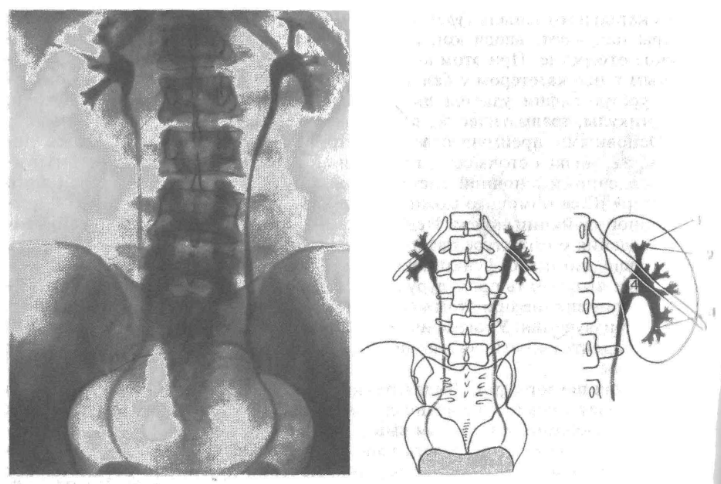

Экскреторная урография при нефроптозе: диагностические изображения